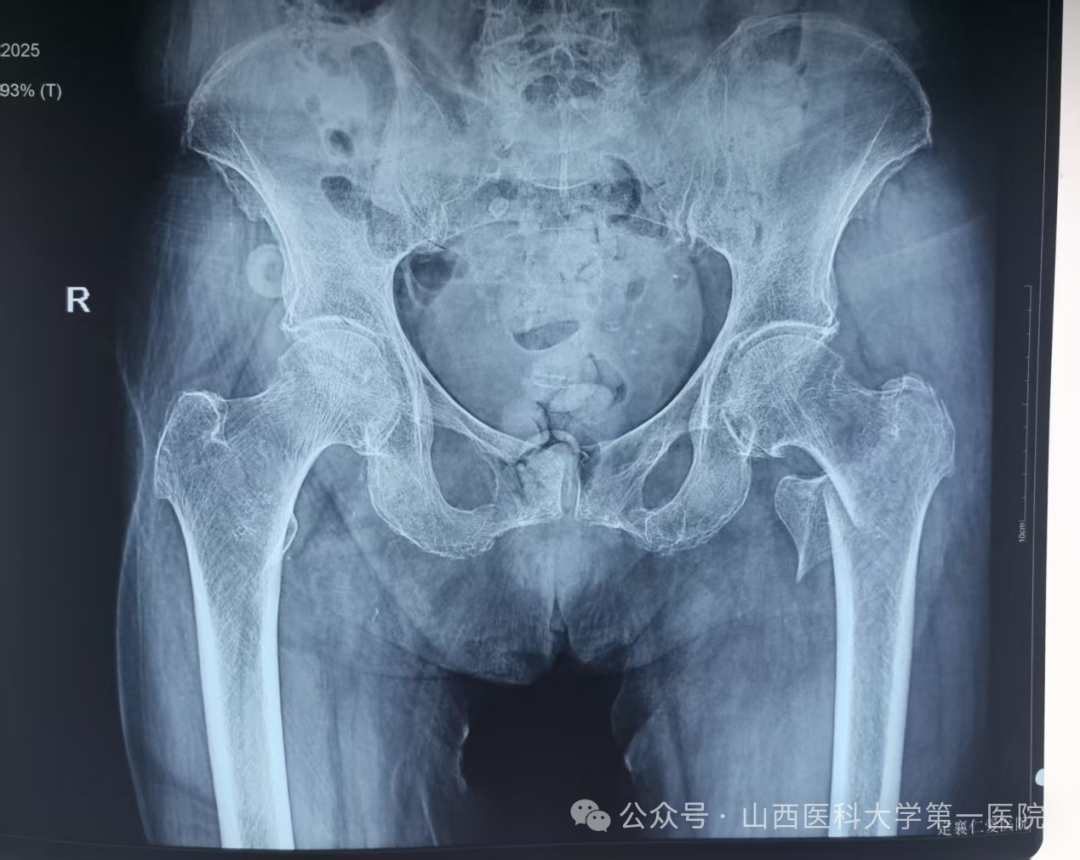

近日,患者李某某在即将迎来自己103岁生日时,不慎在家摔倒导致左髋关节疼痛伴活动受限,就诊于当地医院诊断为左侧股骨转子间骨折,因患者为超高龄老人,当地医院考虑手术风险大,建议转诊上级医院进行治疗。患者家属遂联系120转诊至山西医科大学第一医院就诊,骨科主任杨自权评估患者病情后建议手术治疗。

为防止坠积性肺炎、褥疮、深静脉血栓等并发症发生,杨自权主任团队在患者入院后,积极完善术前准备,经过医务处的组织和血管外科、麻醉科、康复科等多学科的MDT合作,手术时间定于患者入院第三天。2022年,美国AAOS(美国骨科医师协会)指南强烈推荐老年股骨转子间骨折(稳定或不稳定)采用髓内钉内固定。因此,杨自权主任团队拟行股骨转子间骨折闭合复位髓内钉内固定微创手术。

手术当日,杨自权主任团队借助丰富的手术经验,术前在牵引床、G臂辅助下迅速给予患者闭合复位骨折断端,结合经典的“2-1-1”微创手术切口实施手术,手术过程顺利,G臂透视可见骨折复位满意,髓内钉位置满意。术后患者顺利出院,安返家中。